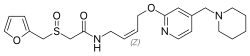

Принята следующая классификация H2-блокаторов по поколениям[4]:

- I поколение — циметидин,

- II поколение — ранитидин,

- III поколение — фамотидин,

- IV поколение — низатидин,

- V поколение — роксатидин.

Ранитидин имеет меньше типичных для циметидина побочных эффектов, а препараты последующих поколений — ещё меньше. При этом активность фамотидина в 20—60 раз превышает активность циметидина и в 3-20 раз активность ранитидина. По сравнению с ранитидином фамотидин более эффективно повышает pH и снижает объем желудочного содержимого. Длительность антисекреторного действия ранитидина — 8-10 часов, а фамотидина — 12 часов[1].

H2-блокаторы IV и V поколений низатидин и роксатидин на практике мало чем отличаются от фамотидина и не имеют перед ним существенных преимуществ, а роксатидин даже немного проигрывает фамотидину в кислотоподавляющей активности[4].